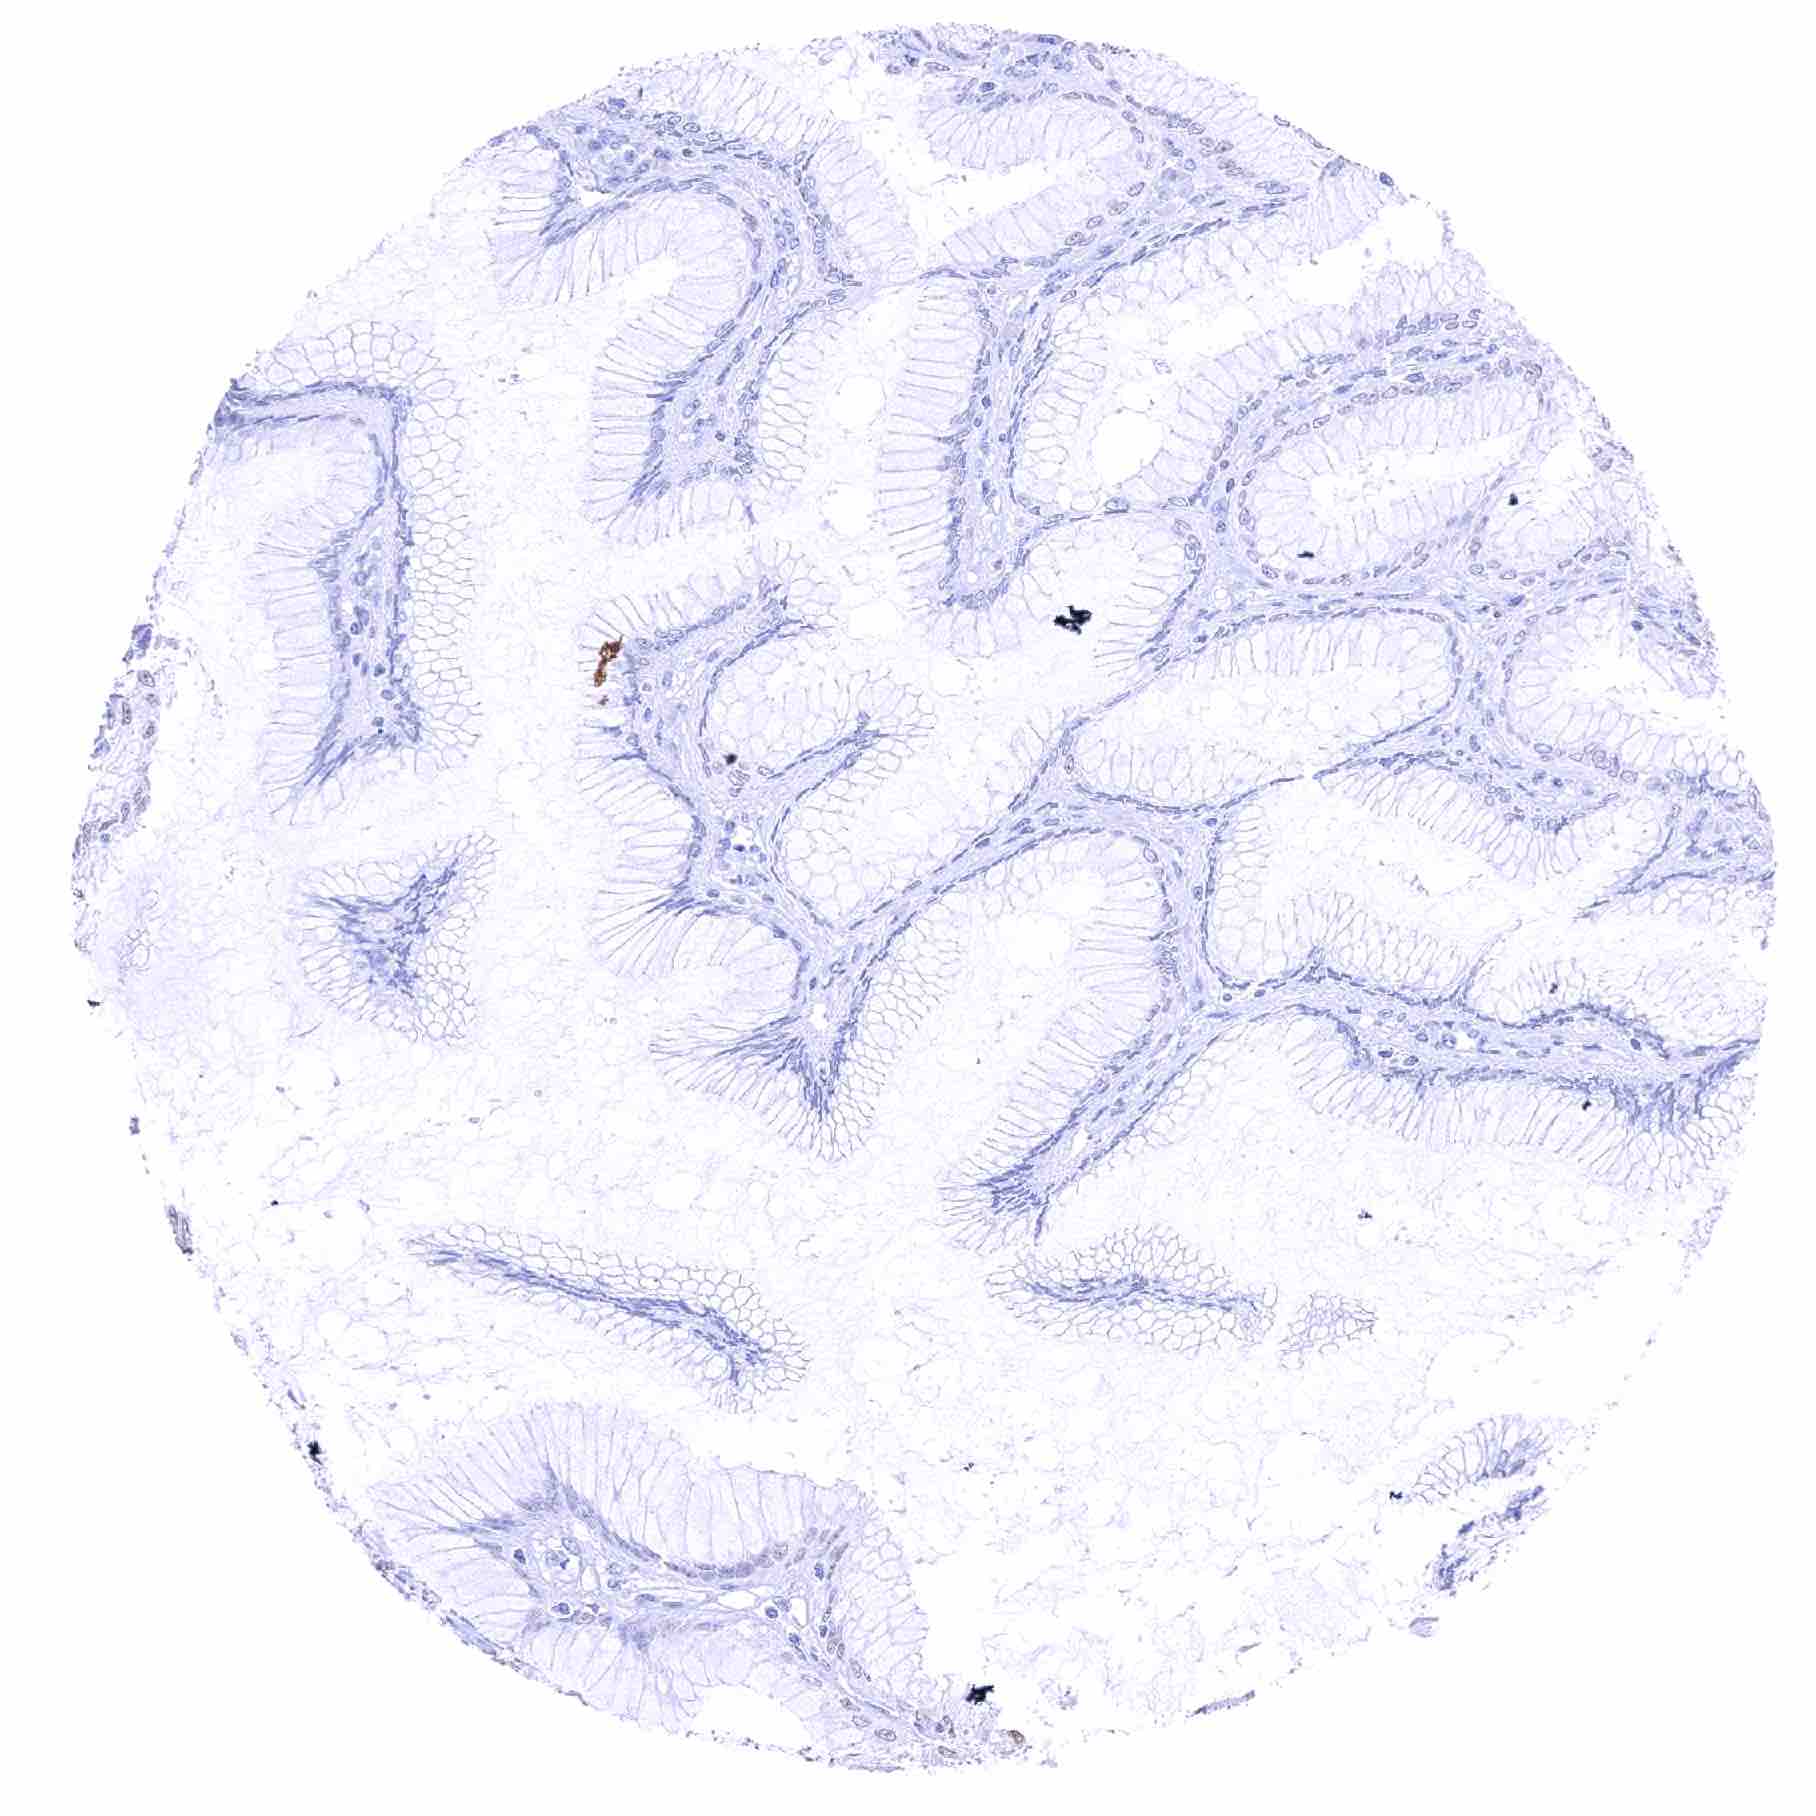

Duodenum, mucosa